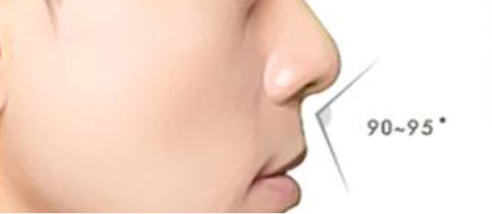

Dental Condition: Protruded side profile

(Facial Profile Analysis)

In the right hands, braces can also subtly improve overall facial harmony and aesthetics (while correcting underlying jaw and tooth alignment issues).

Not guided just by a feeling, but an artistic process guided by scientific measurements.

Unlike metal braces that often rely on extraction to create space, clear aligners allow gentle arch expansion and digitally planned movement (distalization etc) to ensure the least compromise in facial profile.

Perfect if your facial profile makes you unsuitable for extraction.